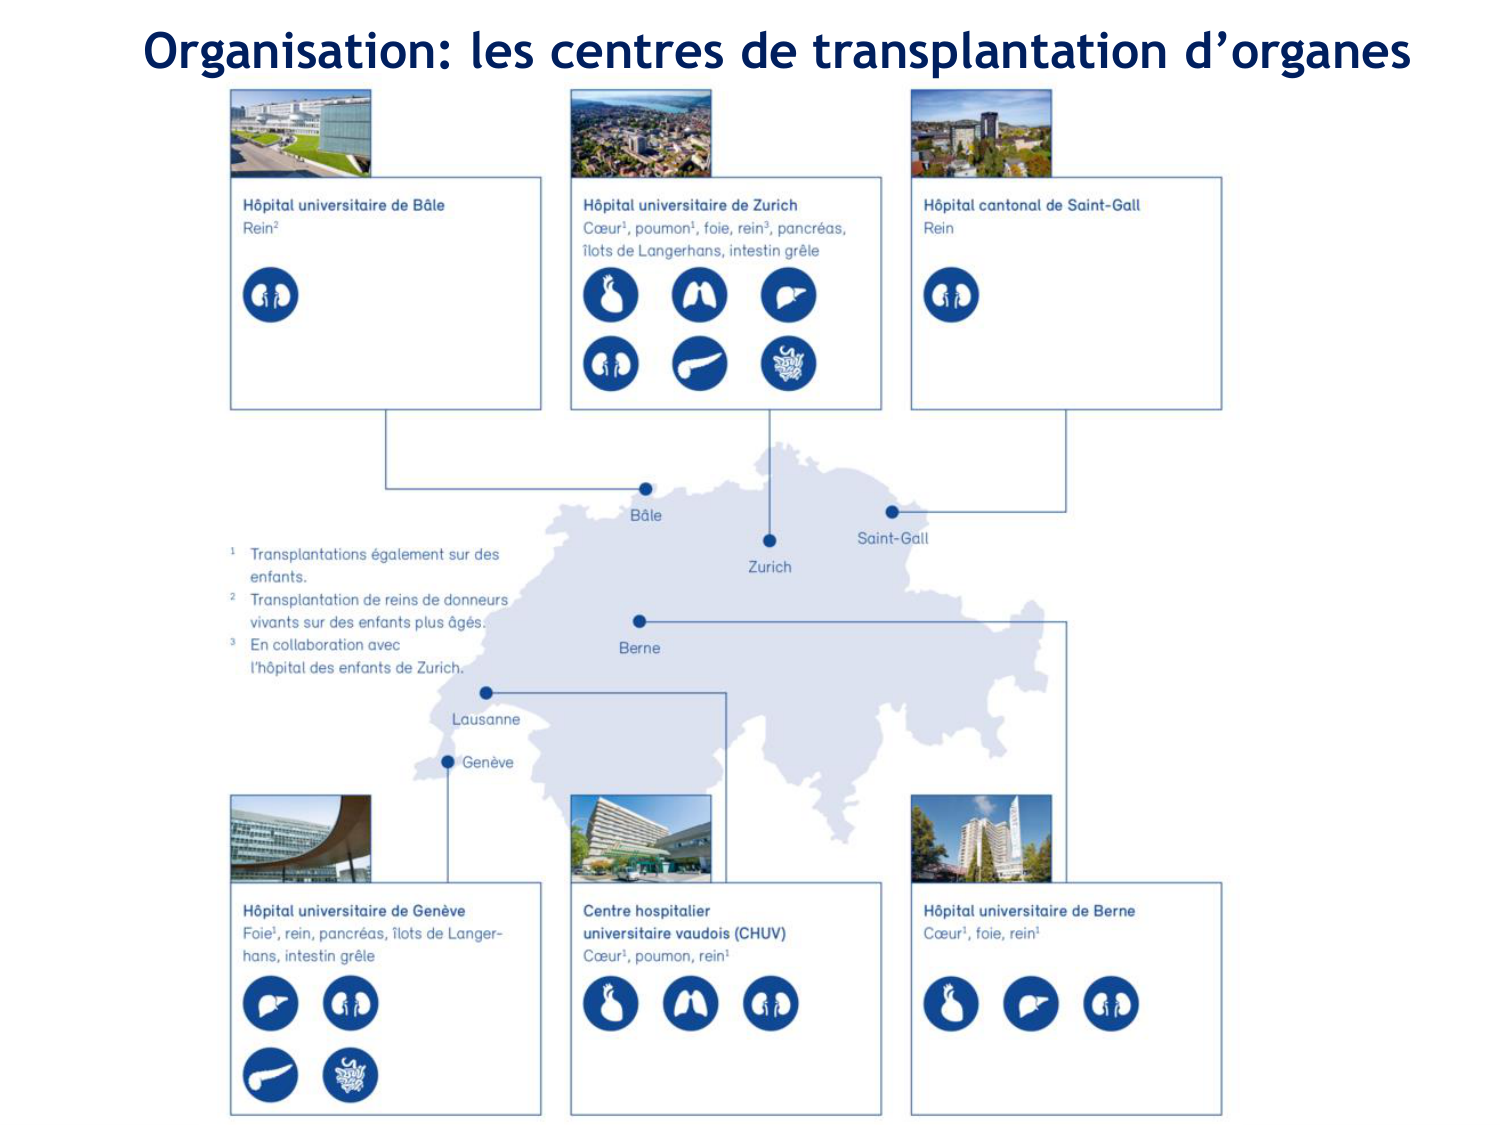

SMB4 Systèmes physiologiques 2 Immunologie, inflammation, transplantation · 61 pages · 8 sections